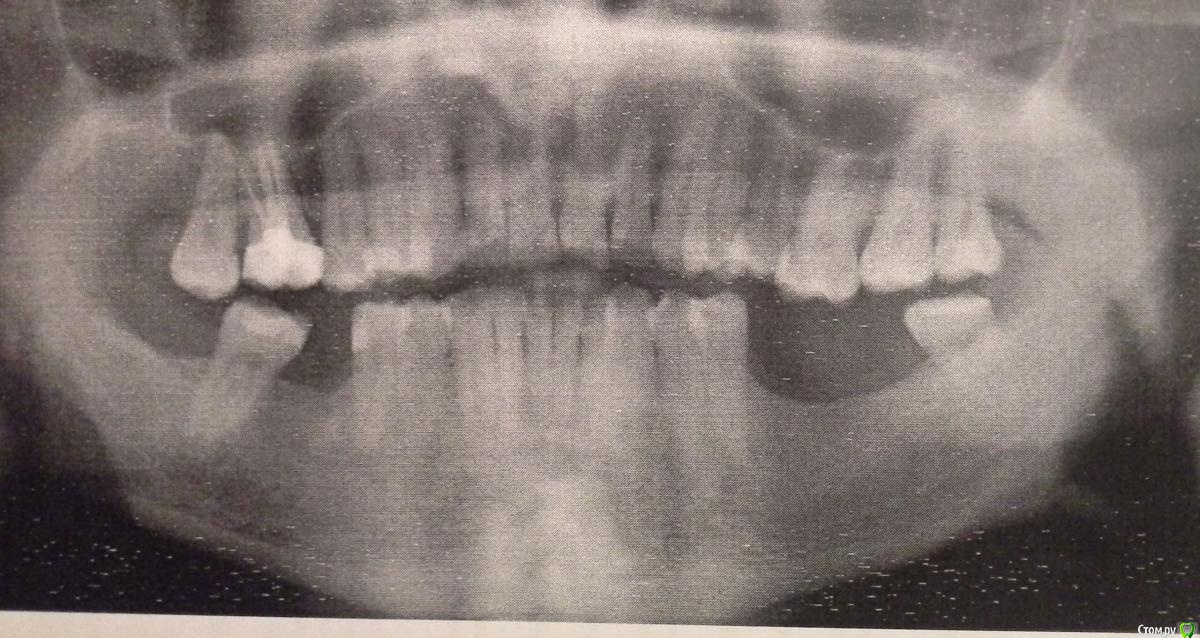

stanson Опубликовано 31 октября, 2015 Поделиться Опубликовано 31 октября, 2015 Побывал у двух врачей по поводу установки 3х имплантов на жевательные зубы нижней челюсти. Первый предложил поставить 3 импланта astra tech.Коронки на них с винтовым креплением, а не цементным.Сказал, что так удобнее заменить коронку в случае проблем с ней.Так ли это?Там где нет одного зуба крайний предложил немного сточить чтобы нормально поставить коронку(крайний зуб ушел в сторону).Других методов обойти эту проблему нет ? Второй врач предложил поставить 3 импланта alpha bio. Причем там где нет 2х зубов рядом (слева снизу)предложил поставить два импланта и мост на эти импланты. А на мост сделать 3 коронки.Причем под этим мостом ранее было ДВА зуба.Мотивирует тем что дословно "наличие двух крупных искусственных зубов может смотреться не очень эстетично".Стоит ли заморачиваться с мостом? Ссылка на комментарий

carloss Опубликовано 31 октября, 2015 Поделиться Опубликовано 31 октября, 2015 (изменено) Если хотите, чтобы было очень хорошо, то нужна еще ортодонтия(брекеты) - там где внизу не хватает одного зуба, последний зуб действительно сильно наклонился и что еще хуже, выдвинулся вниз его антагонист, верхний 7 зуб. И он будет еще продолжать опускаться, что приведет к проблемам как с ним самим, так и с соседними и зубами, и возможно к серьезным проблемам с прикусом и жеванием вообще. Советую хотя бы проконсультироваться у ортодонта, узнать за и против. Имплантат там безусловно нужен, но если по каким-то причинам, не захотите полноценное ортодонтическое лечение, то хотя бы нужно тот самый наклоненный седьмой зуб, немного "задвинуть" обратно(есть такие техники частичной ортодонтии на одну сторону, часто с опорой на соседний имплантат) и подточить, и поставить пломбу, или лучше коронку на верхний седьмой. С другой стороны ситуация немного попроще, но верхняя шестерка тоже немного опустилась(хотя бы подточить и пломбу перед окончательным протезированием). Кость скорей всего наращивать не обязательно, а десну, наоборот - надо. Изменено 31 октября, 2015 пользователем carloss 1 Ссылка на комментарий